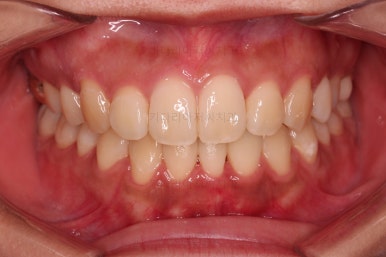

중앙선, 교합, 앞니 맞물림 등 모든 것이 좋아졌네요.

이제 부산재교정 전후 비교를 해볼게요.

교합, 정중선 모두 좋아졌고요.

입도 약간 더 들어가면서 예쁜 옆라인이 되었네요.

웃을 때 한 쪽으로 쏠려있던 중앙도 개선되어 예뻐졌고, 치아 높낮이도 조절하여 웃을 때 보이는 앞니의 길이도 매우 예븐 정도로 조절이 되었습니다.